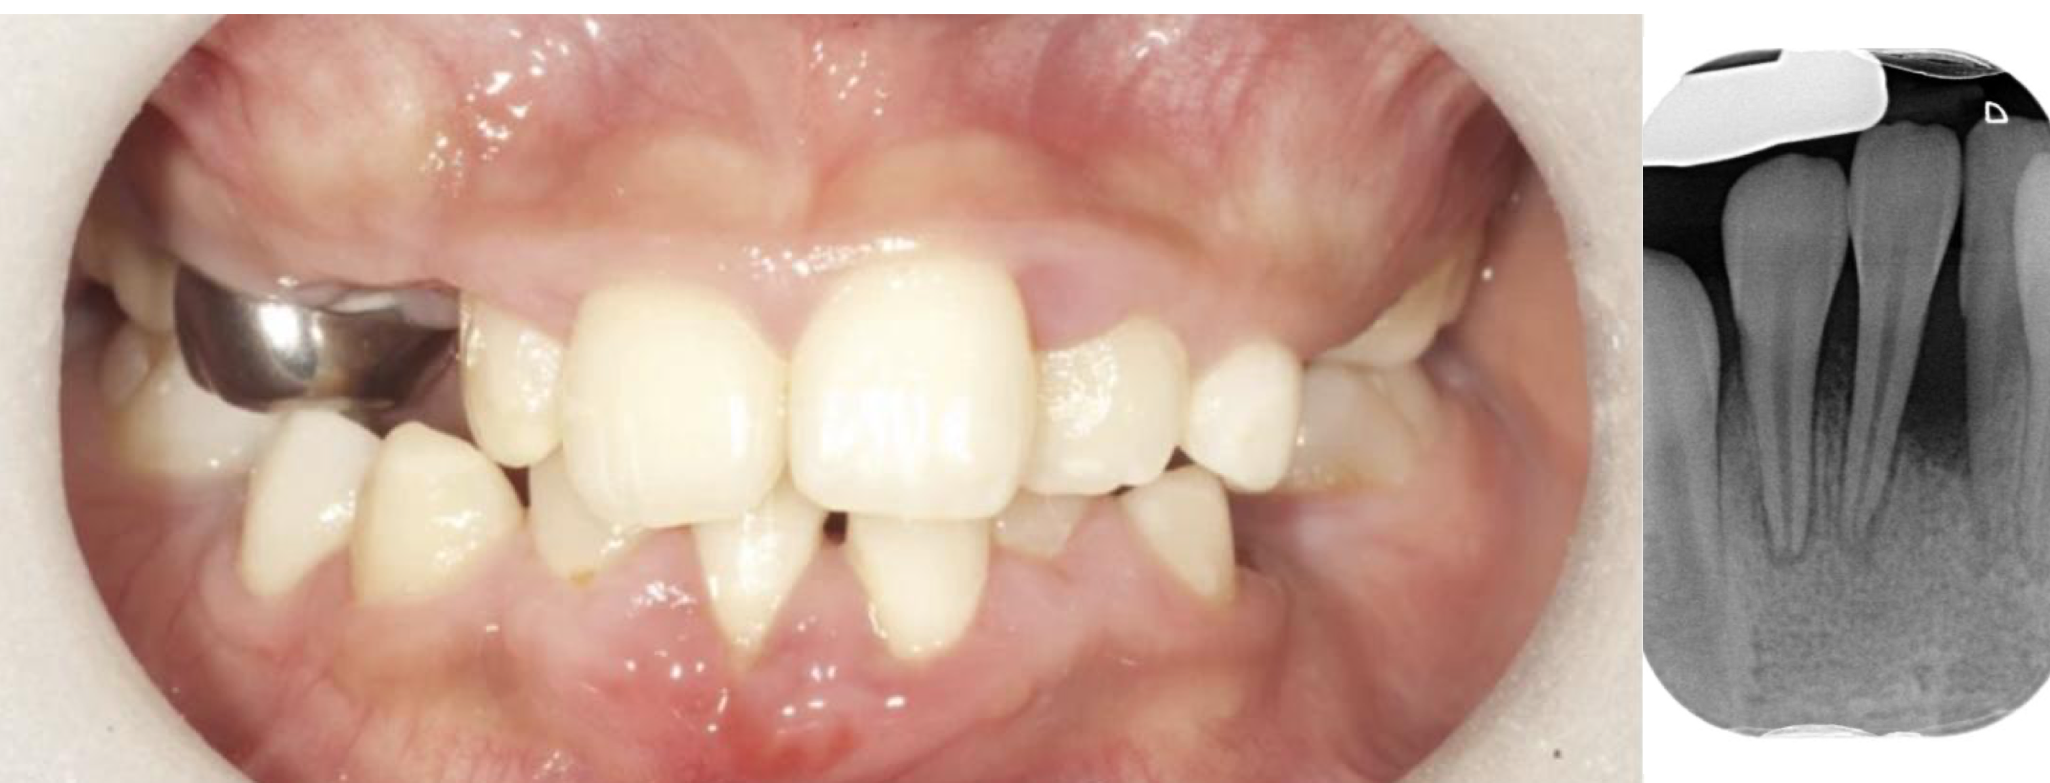

By the time she was 24 months, her front teeth came out—most of her baby teeth have fallen out randomly

Clinical exam:

Teeth #E, F, O, P missing, no clinical caries

Teeth #D & G: Class II mobility

Mild localized gingivitis

Radiographic exam

Enlarged pulp chambers

Atypical appearance of clinical crown of the permanent molars

Thin dentin

Horizontal alveolar bone loss

HPP